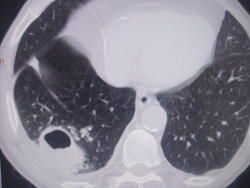

Больной лечился у невролога, провели проф ФГ- выявили деструктивную пневмонию, пролечилили, на Р контроле- ухудшение, клиники абсцесса не было, была боль в гр клетке спереди справа. Из анамнеза- лечился оперативно 6-7 лет назад по поводу рака верхней губы, в ООД не наблюдался последние годы. Данные за туб этиологию сомнительны, как мне кажется, очагов отсева по слоям не вижу,  хотя мож не так смотрю. Ваше мнение коллеги, абсцесс это или нет?

Вполне может быть и полостной формой рака с периканкрозной пневмонией. Пока исследуют мокроту на БК, АК и микрофлору с чувствительностью к антибиотикам, пока лечат, придёт время и для КТ-контроля после лечения. В зависимости от рукастости хирургов, можно было б и пропунктировать - но тут в каждом монастыре свой устав)).

По опыту хочу сказать, что в настоящее время классической клиники абсцесса можете и не увидеть. Очень она изменилась. В данном случае контроль  должен помочь. В связи с тем, что стенки имеют разную толщину и вокруг почти нет изменений, больше склоняюсь к полостной форме рака.